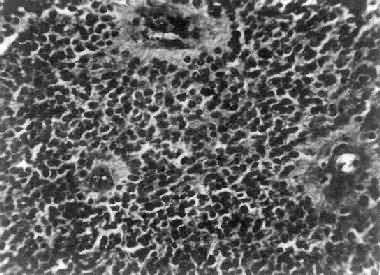

肉眼观,瘤组织呈鱼肉状,色灰红。镜下,肿瘤由圆形、椭圆形或胡萝卜形细胞构成,胞核着色深,胞浆少而边界不清楚,有多少不等的核分裂像。细胞密集,间质中有纤细的纤维,血管不多。瘤细胞环绕一个嗜银性纤细的神经纤维中心作放射状排列形成典型的菊形团(图16-26),这对髓母细胞瘤的病理诊断有一定的意义。瘤细胞具有向神经元及神经胶质双向分化的潜能,既能向神经母细胞、节神经细胞分化,也能向胶质母细胞、星形胶质细胞分化。如瘤细胞侵入软脑膜,可在蛛网膜下腔脑脊液中广泛播散转移。

图16-26 髓母细胞瘤

瘤细胞较小,着色深,密集排列,有菊形团形成